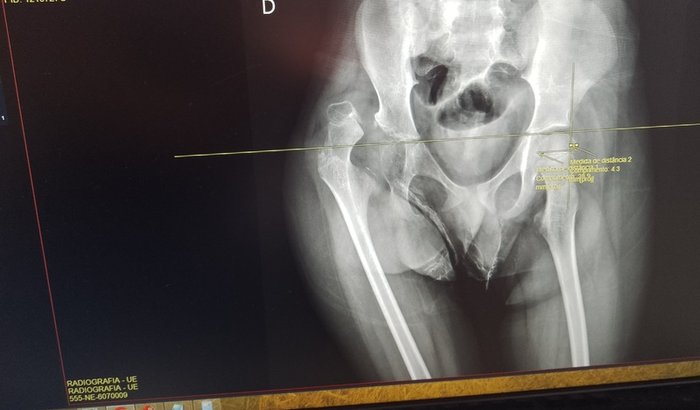

ola sou a mãe do Yago presisamos arrecadar pra ajudar nos custos de ir até o hospital Yago está internado no HC campus de Ribeirão motivo ele fez uma cirurgia no quadril em agosto presizou tirar a cabeça do fêmur te lá pra cá o Yago só chor ver tudo

ola sou a mãe do Yago presisamos arrecadar pra ajudar nos custos de ir até o hospital Yago está internado no HC campus de Ribeirão motivo ele fez uma cirurgia no quadril em agosto presizou tirar a cabeça do fêmur te lá pra cá o Yago só chora de dor essa semana descobrimos que ele está com um desgaste uma possível doença na parte ossea ésta aguardando cirugia não tenho condições de me locomover até o hospital todos os dias pois estou desempregada e não tenho condições Yago presisa  de produto de higiene  e seus irmãos em casa também presisam.ajuda  nos custos da passagem qualquer ajuda será bem vinda meu pix 16994141553 Caroline Queiroz nascimento